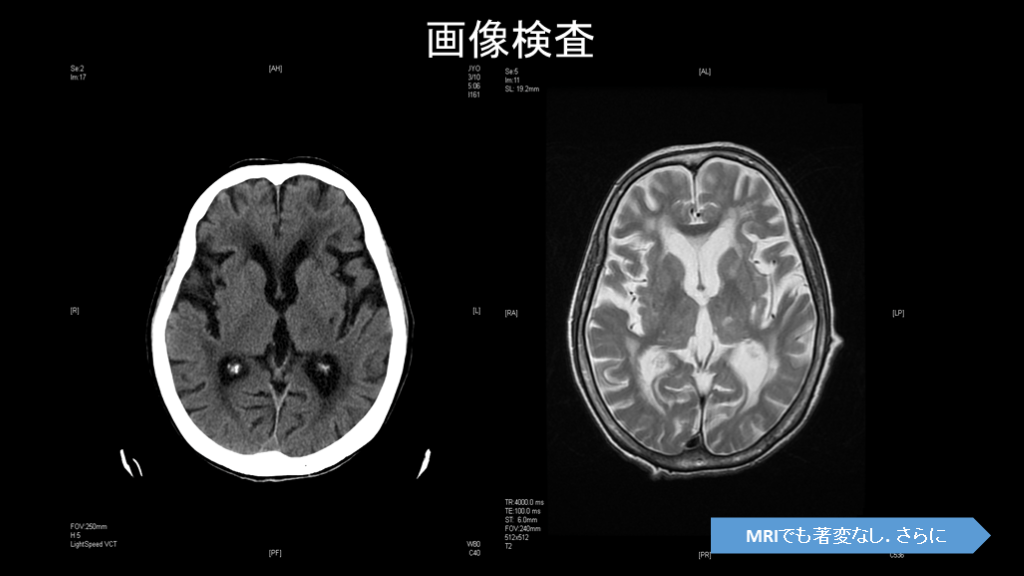

画像検査と髄液検査の重要性

#11.

画像(脾臓腫瘍、慢性水腎症)上は以前と大差なし 神経因性膀胱・水腎症

画像検査 MRIでも著変なし. さらに